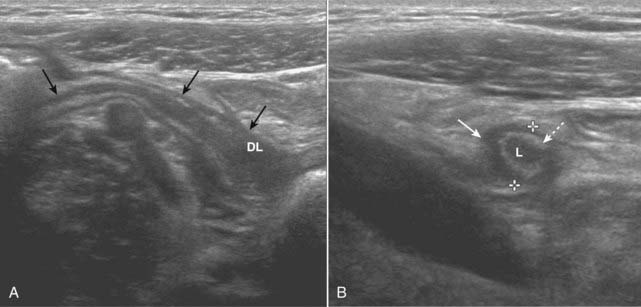

imageIn acute appendicitis, the appendix may be recognized on ultrasound as a blind-ending, aperistaltic tube with a diameter of 6 mm or more. The appendix is noncompressible (using a technique called graded compression). It may be tender when palpated with the probe. In about a third of the cases of appendicitis, a fecalith will be present (Fig. 19-25).

image

Figure 19-25 Acute appendicitis, sagittal and transverse views.

A, There is a blind-ending tubular structure (solid black arrows) that has a thick wall and a distended lumen (DL) representing an inflamed and distended appendix. B, In this transverse view, the appendix (solid white arrow) measures 7 mm between marks (normal <6 mm). The lumen (L) contains fluid, and there is an echogenic ring that represents the mucosa (dotted white arrow) surrounding it. The appendix may be tender when palpated with the probe.